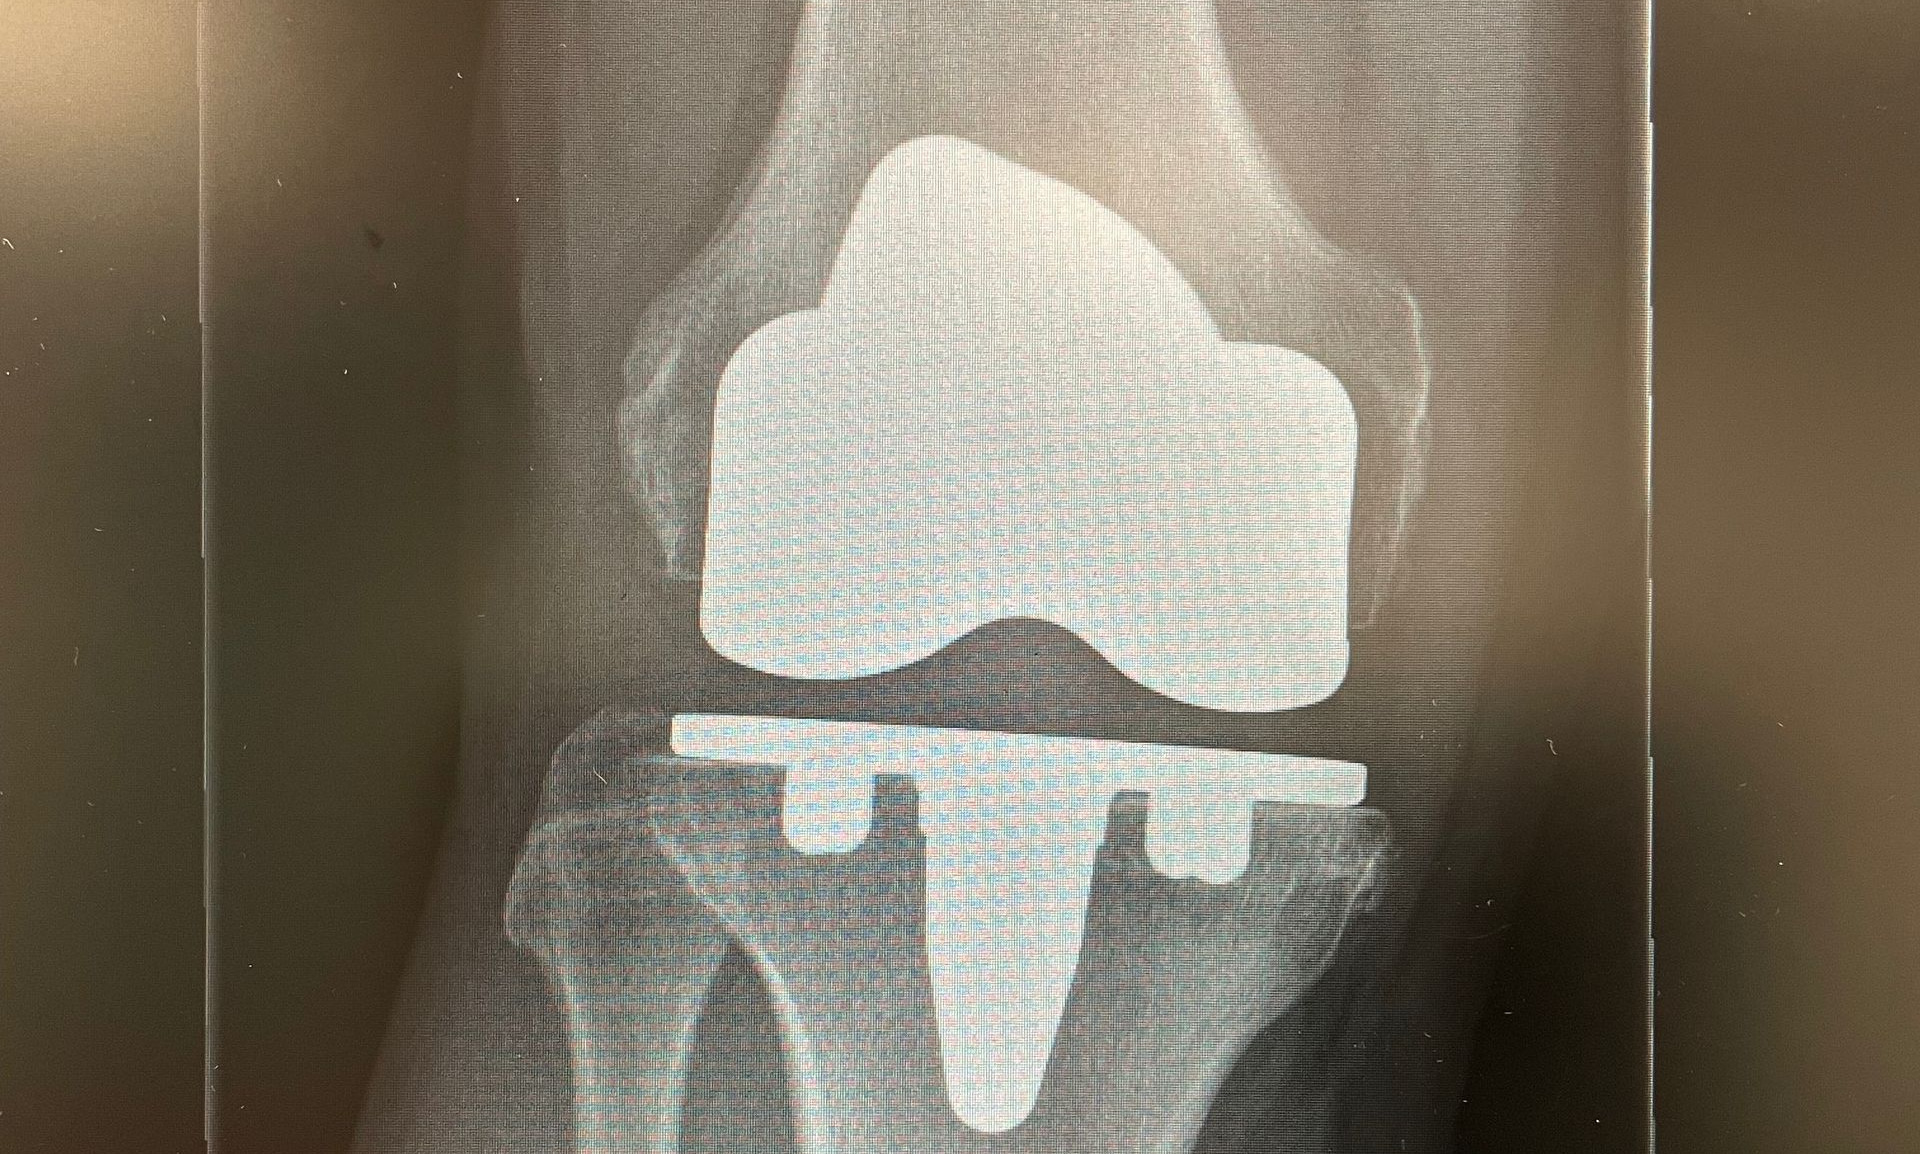

Cementless Knee Replacement

Mr Wall is now able to offer DePuy Attune Cementless total knee replacements through his private practice at Nuffield and Spire Hospital Leeds.

This technique allows the latest generation of total knee replacements to undergo

complete bio-integration for optimal long-term results.